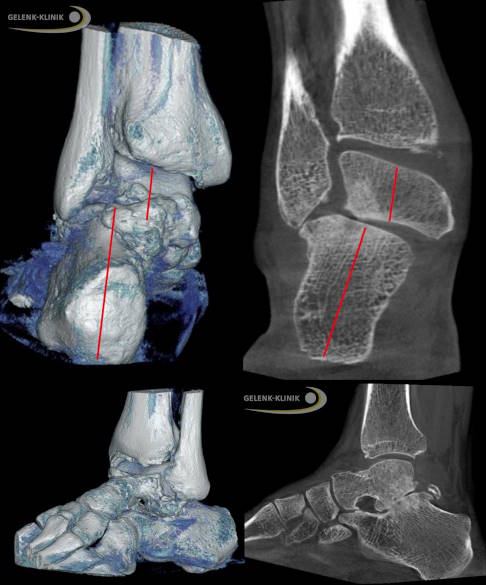

Die Instabilität des Fersenbeins gegenüber dem Sprungbein ist eine typische Indikation für die subtalare Arthrodese. In dieser Aufnahme (links: digitale Volumentomographie mit 3-D Darstellung (DVT), rechts die Schichtauswertung der DVT) ist eine deutliche Verschiebung des Fersenbeines nach außen mit Kontakt zwischen Fersenbein und Wadenbein zu sehen. Außerdem erkennt man eine fortgeschrittene Arthrose und Fehlstellung des übrigen Fußbereiches. Solche Veränderungen führen zu einer massiven Instabilität. © Gelenk-Klinik